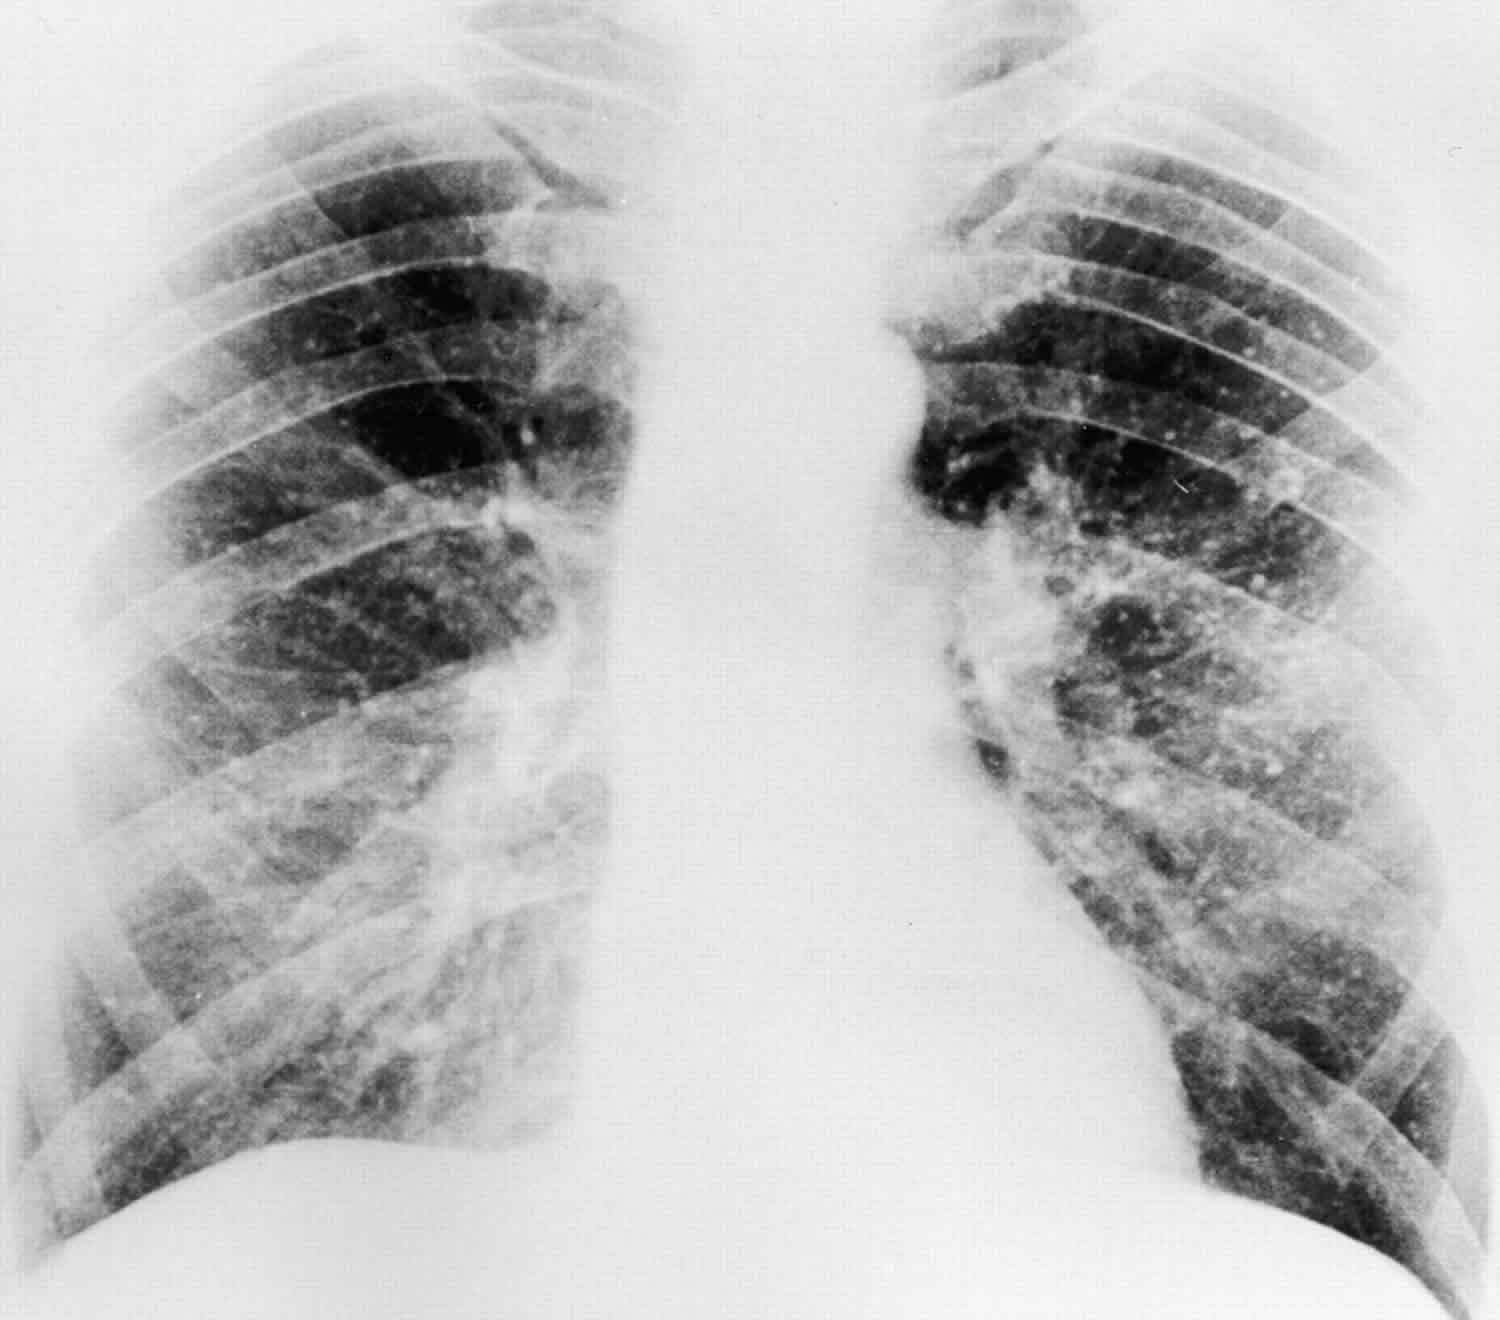

Chest xray, PA view showing moderate calcification of the aortic arch What Does Moderate Calcification Mean Although the presence of cac can help predict the presence or absence of coronary artery. Coronary artery calcifications occur when calcium builds up in the arteries that supply blood to the heart. Coronary artery calcification occurs when calcium deposits and other compounds build up in a person’s coronary artery. It measures the amount of calcified plaque (calcium) inside the walls. What Does Moderate Calcification Mean.